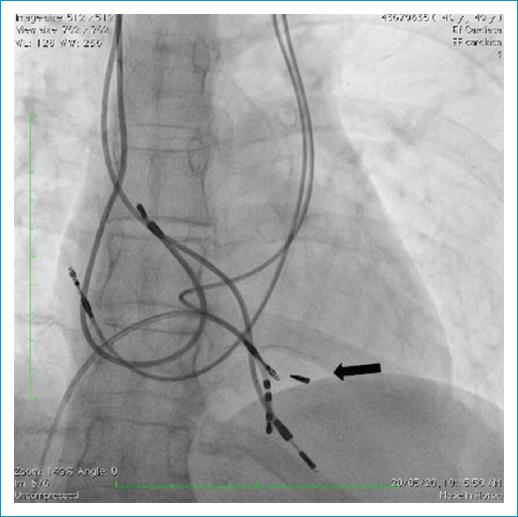

Bajo anestesia general se realizó punción de la vena femoral común derecha y a través de esta se posicionó catéter cuadripolar en el ápex del ventrículo derecho (Fig. 1). Luego, se realizó disección por planos anatómicos hasta la región subpectoral izquierda de donde se explantó el dispositivo y con ayuda de un electrobisturí se liberó el electrodo hasta la región infraclavicular izquierda, posición en la cual se realizó una sutura hemostática. Previa verificación de la integridad del lumen, se cortó el electrodo en la porción distal y a través del lumen se avanzó un Lead Locking Device (LLD) de Spectranetics® (Phillips, Colorado Springs, USA) y sobre este se avanzó vaina de corte rotacional mecánica TightRail 13 Fr de Spectranetics® hasta la porción más proximal del electrodo (pasando por la vena subclavia y la vena cava superior izquierda persistente) y con ayuda de contra-tracción se extrajo casi la totalidad del electrodo, dejando remanente menor de 1 cm (Fig. 2). Antes de retirar la vaina, se avanzó guía 0.032” de 1.5 m, y con técnica de guía retenida se realizó implante de marcapasos bicameral definitivo, sin documentarse estimulación diafragmática a máxima salida (Fig. 3). Debido a que los demás electrodos no estaban generando complicaciones de ningún tipo, no se intentó su extracción.

Figura 3 Radiografía de tórax posextracción instrumentada de cable VDD e implante de marcapasos bicameral definitivo. Proyección PA en la que se observa el resultado final. En la flecha se muestra fragmento residual del electrodo retirado. Se observan los dos cables previamente abandonados y los dos nuevos electrodos implantados.